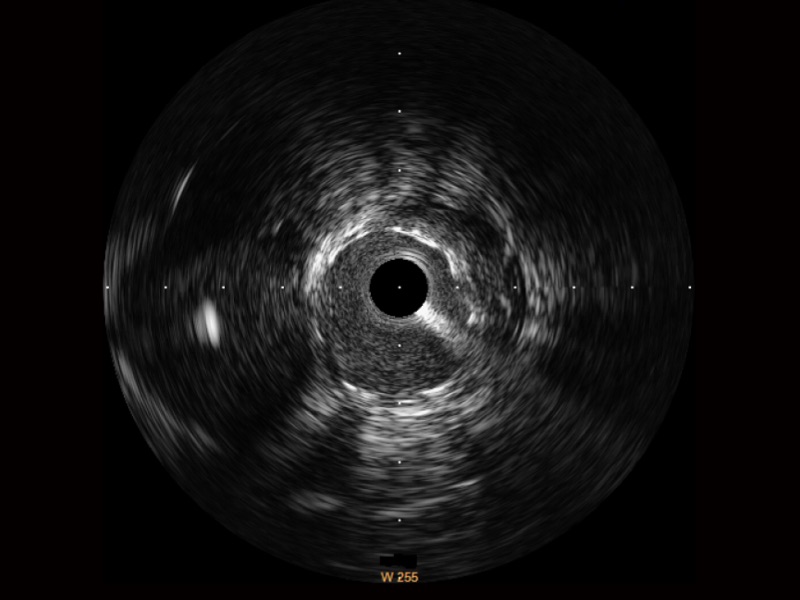

16877太阳集团宽频IVUS图像

传统IVUS图像

对比传统IVUS导管成像,16877太阳集团宽频IVUS图像的近场支架梁显影更细腻,远场中膜外血管仍清晰可辨,兼顾远中近,兼顾分辨力与穿透深度